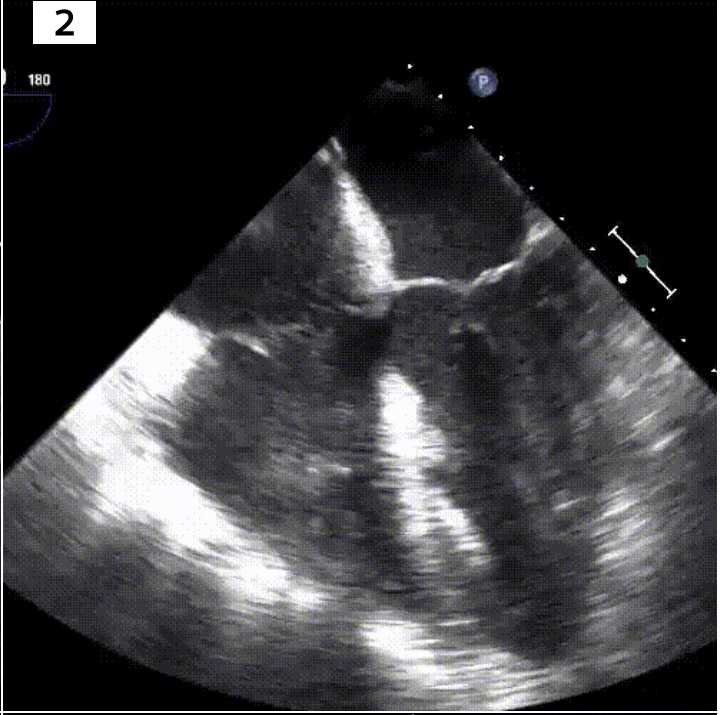

Identify the view and structures of interest

Midesophageal 4 chamber view.

What transducer angle do you need to get ME4C view?

0-10*